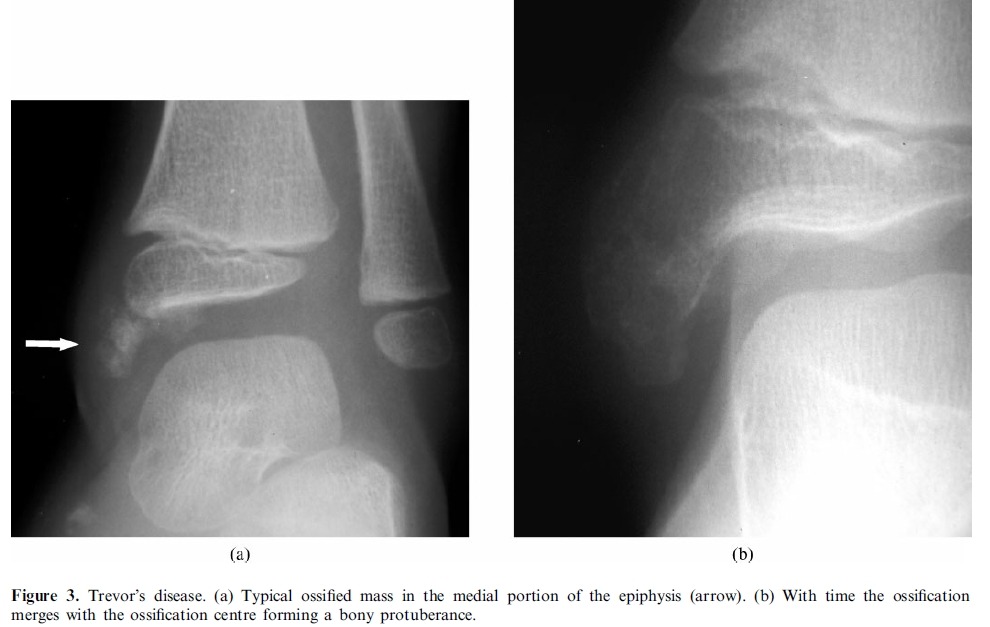

Trevor’s disease